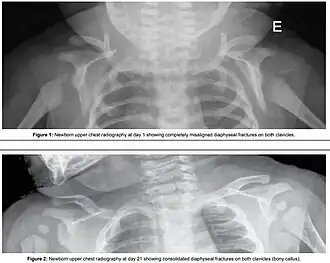

Fracture of both clavicles as a result of shoulder dystocia (top) – Post healing (bottom)